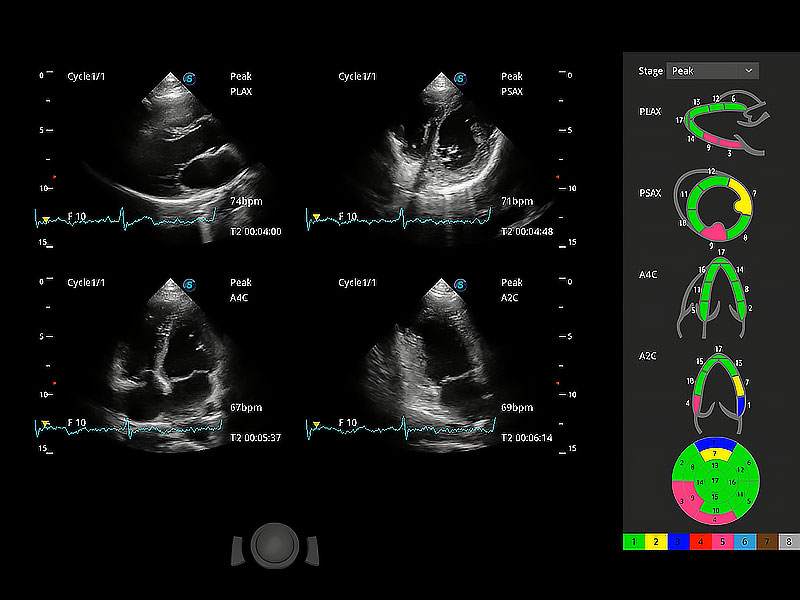

ProPet 80 配備了豐富的心臟探頭群、先進(jìn)的成像技術(shù)和專業(yè)的心臟測(cè)量工具,可幫助動(dòng)物醫(yī)生為不同體型和生理結(jié)構(gòu)的動(dòng)物提供心臟和心肌功能的全面評(píng)估。

通過心肌識(shí)別技術(shù)與二維斑點(diǎn)追蹤技術(shù)相結(jié)合,對(duì)心臟的超聲圖像進(jìn)行量化分析。計(jì)算心肌17個(gè)節(jié)段的應(yīng)變、應(yīng)變率、速度、位移等,并通過牛眼圖的形式進(jìn)行呈現(xiàn)。

具備多種協(xié)議可選,同時(shí)支持17階段劃分法和專業(yè)的SE報(bào)告。